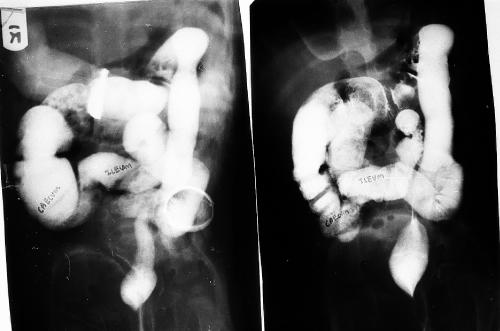

Benign ureteral polyps, also known as fibroepithelial polyps, can cause upper urinary tract obstruction by growing to block the flow of urine from the kidney. Fibroepithelial polyps are very rare benign lesions originating from the mesoderm. We have presented an interesting and unusual case who…...